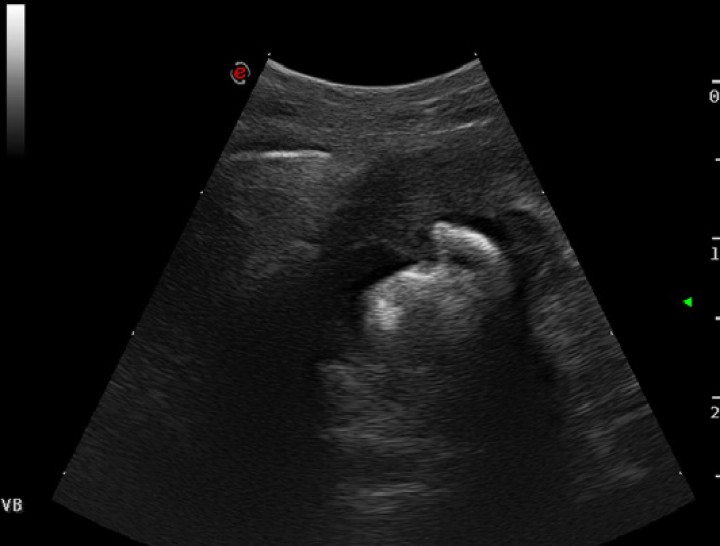

Al realizar una ecografía en la zona de la fístula, se evidenció que el trayecto fistuloso se dirigía en profundidad hacia la zona de la vesícula biliar, encontrándose la pared de la misma aumentada de grosor y con su interior ocupado por estructuras minerales que emitían sombra acústica (Fig. 4).

<p>Imagen ecográfica de la vesícula biliar. Se visualiza la pared engrosada con cálculos en su interior.</p>

Imagen ecográfica de la vesícula biliar. Se visualiza la pared engrosada con cálculos en su interior.